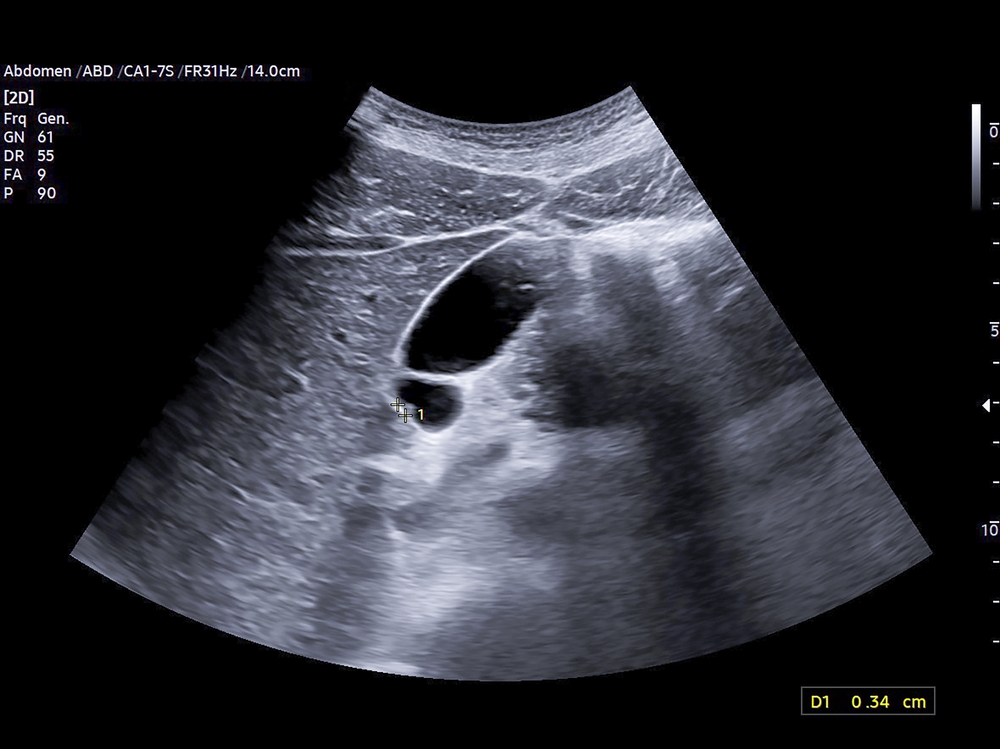

Tulžies pūslė įsikūrusi po kepenimis dešinėje pilvo pusėje. Šis kriaušės formos organas kaupia kepenų išskiriamą tulžį, padedančią virškinti riebalus. Įtariant tulžies pūslės sutrikimus, gydytojas gali pasiūlyti atlikti echoskopiją.

Dažniausiai tyrimas skiriamas, jei įtariami tulžies akmenys – kieti dariniai iš tulžies, kurie neretai sukelia nemalonų jausmą, pilvo ar nugaros skausmą, pykinimą. Dar viena dažna priežastis – uždegimas arba infekcija (vadinama cholecistitu), kuris gali išsivystyti, užsikimšus tulžies latakams.

Atliekant tyrimą, pacientas atsigula ant nugaros. Ant pilvo odos užtepamas specialus gelis, kuris padeda garso bangoms sklisti be oro tarpų tarp odos ir daviklio. Tuomet specialistas švelniai perkelia daviklį per pilvo sritį – prietaisas siunčia ir priima garso bangas, kurios paverčiamos vaizdais, leidžiančiais įvertinti tulžies pūslės formą ir būklę.